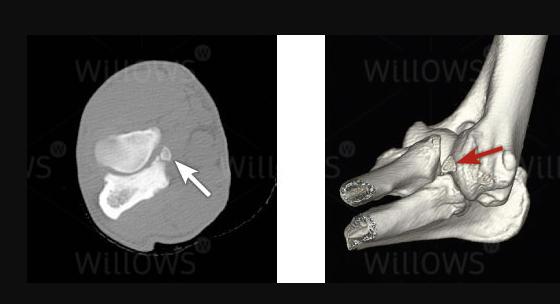

关节软骨无法在特定位置转变为骨骼,直接令到这区域的软骨增厚,增厚的软骨与周围正常的软骨分离形成了皮瓣,这一系列过程便称之为OCD。异常软骨的皮瓣有可能会发生从关节表面脱离,形成“关节鼠”。

图为“关节鼠”

那么,什么是“关节鼠”?

这一术语较好理解,意指关节出现病变的时候,在关节软骨内部会有自行脱离的“小碎片”。如前文提到,关节之间有“小碎片”的存在,容易发生疼痛等一系列影响。

距骨滑车位置